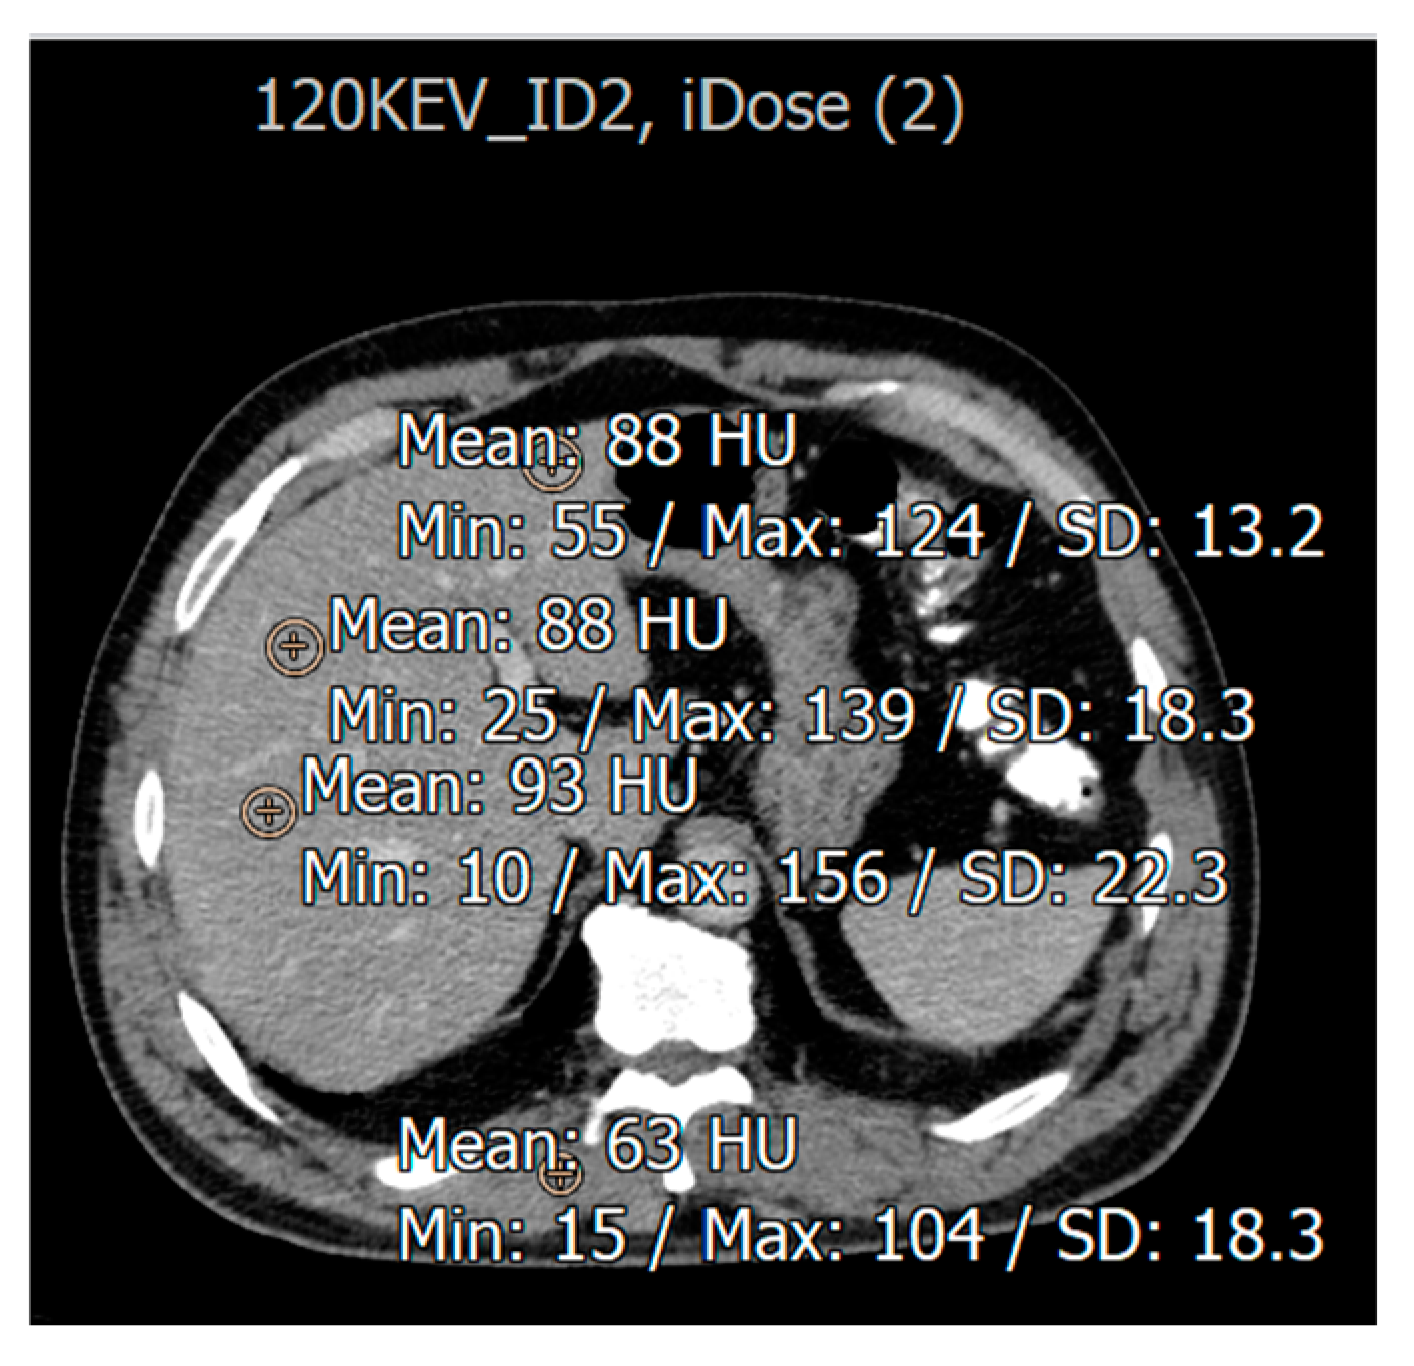

3.2. Evaluation for Patients with Fatty Liver Disease

Image Quality Assessment